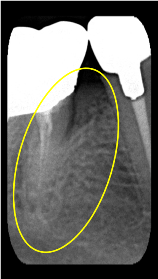

垂直性骨吸収+α-TCP

Perio Wave +Er:YAGレーザー+コールドレーザーの例です。

Perio Wave+Er:YAGレーザー+コールドレーザーで治療した箇所の経過です。

左から直後、1ヶ月経過時、2ヶ月経過時の画像です。